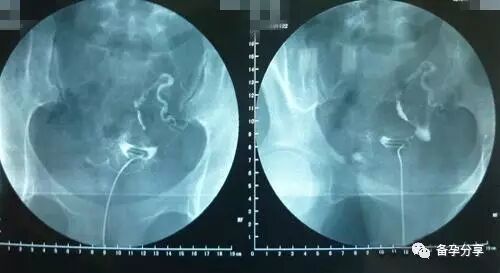

造影检查、宫腔镜检查

像是输卵管造影检查或者是宫腔镜检查,最好都选择月经干净2-7天之间检查,因为这期间内膜厚度还不是很厚,相对检查的身体感受会更轻松,而且宫颈状态也更适合检查。

值得注意的是,这两项检查都要求月经后到检查前都不要安排性生活。而检查结束后最少两周之内不要安排性生活,不要选择盆浴、坐浴等清洗方式,以避免发生炎症感染的情况。